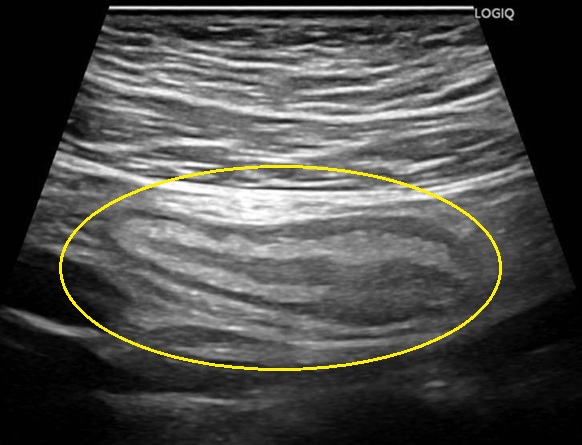

急性虫垂炎の超音波(エコー)画像

- 画像検査(腹部エコー・CT):虫垂腫大、糞石、壁肥厚、周囲の炎症。